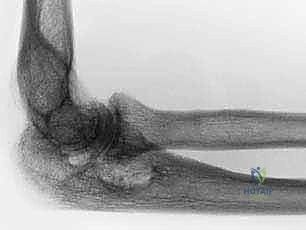

1. التخطيط الجراحي المسبق (Pre-operative Planning)

يتم إجراء صور أشعة سينية دقيقة (X-rays) وأحياناً تصوير مقطعي (CT Scan) لتقييم حجم العظام المتبقية وجودتها. في مرضى الروماتويد، يكون العظم غالباً هشاً (Osteoporotic)، مما يتطلب تخطيطاً دقيقاً لاختيار حجم ونوع المفصل الصناعي المناسب (مفصل متصل Linked أو غير متصل Unlinked).

5. زراعة المفصل الصناعي (Implantation)

يتكون المفصل الصناعي من قطعتين معدنيتين رئيسيتين (جزء عضدي وجزء زندي) وبينهما مفصلة بلاستيكية (Hinge) توفر الحركة السلسة.

يتم تثبيت هذه الأجزاء المعدنية داخل القنوات العظمية باستخدام الأسمنت العظمي الطبي (Bone Cement)، وهو مادة خاصة تضمن تثبيتاً فورياً وقوياً، وهو أمر بالغ الأهمية لمرضى الروماتويد الذين يعانون من هشاشة العظام.

يتم تجميع المفصل الصناعي وربط الجزء العضدي بالجزء الزندي بواسطة مسمار مفصلي (Pin)، مما يعيد للمرفق استقراره المفقود.